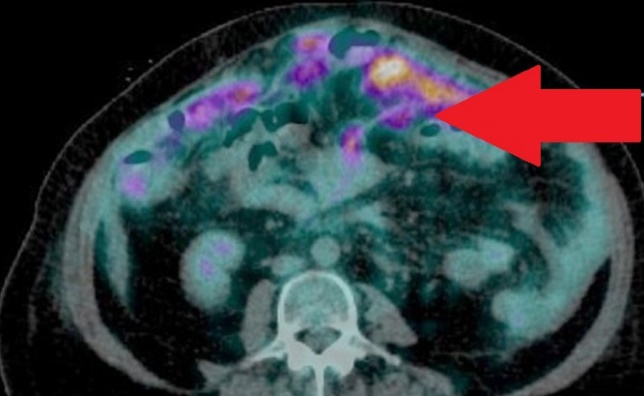

Multiple hepatic metastases — Absolute contraindication for cytoreductive surgery (Courtesy Dr. V. Penopoulos)